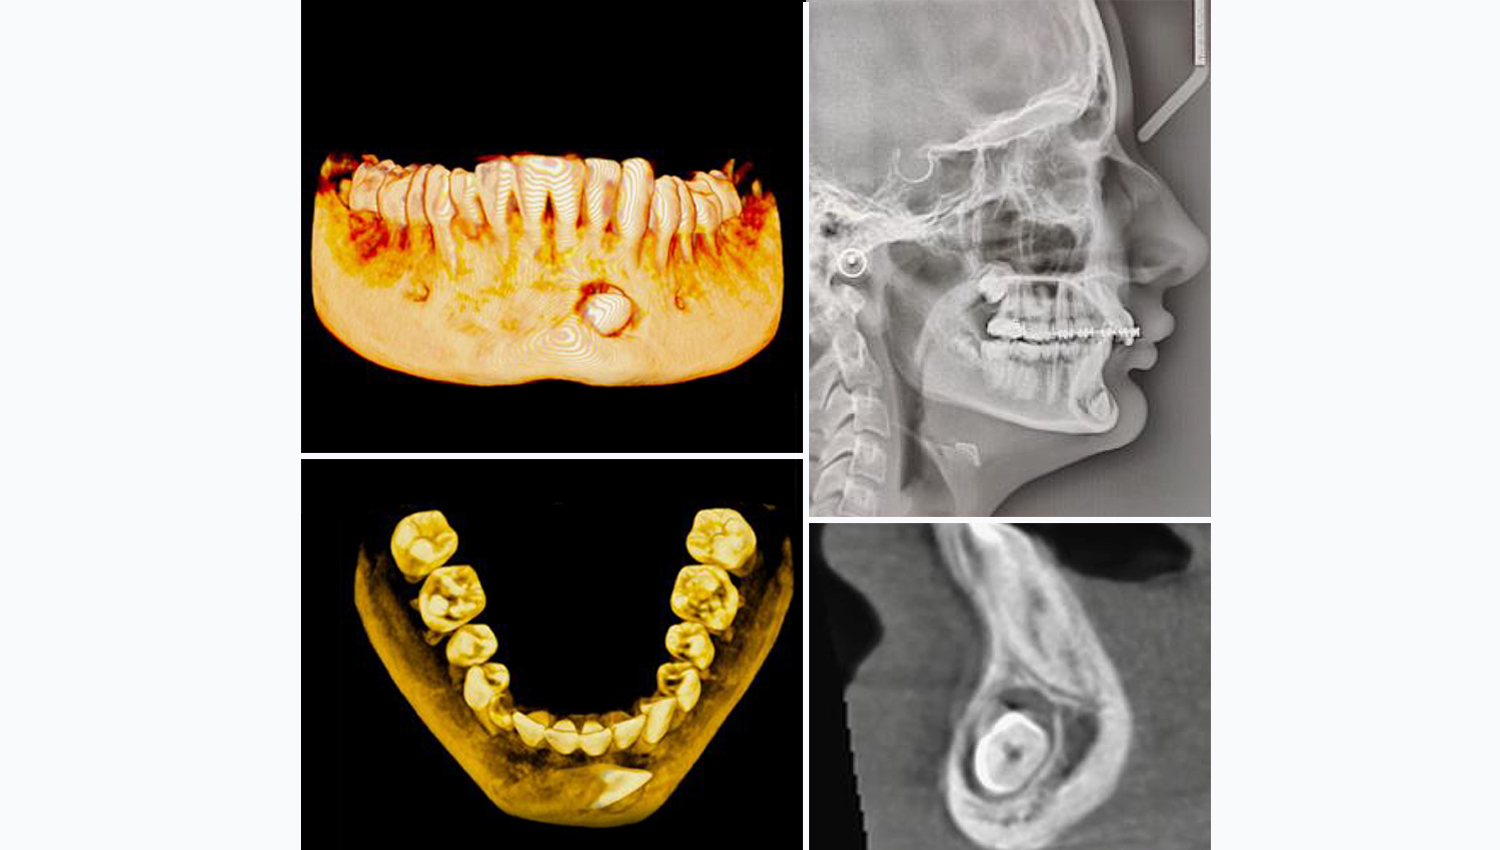

- Feale patient

- 13 years old

- Impacted 33

- Case performed by Dr. Minas Leventis, DDS, MSc, PhD, UK

1.Horizontally impacted 43. Due to its unfavourable position, the tooth cannot be moved orthodontically.